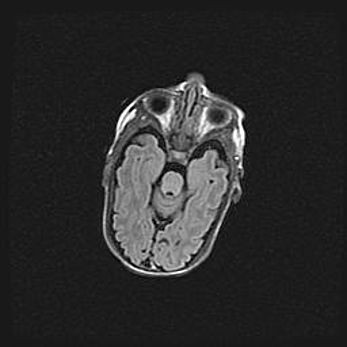

Мальформация Денди-Уокера. Киста задней черепной ямки.

Агенезия мозолистого тела.

Возраст: 2,5 месяца

Вес: 2420 г

Пол: женский

Окружность головы: 37 см

Срок гестации: 32 недели

Мальформация Денди—Уокера — редкий вид патологии ЦНС, представляющий собой врожденный порок развития каудального отдела ствола и червя мозжечка, ведущий к неполному раскрытию срединной (Мажанди) и латеральных (Лушка) апертур IV желудочка мозга. Для этогно синдрома характерна триада симптомов: гипотрофия червя мозжечка и/или полушарий мозжечка, кисты задней черепной ямки, гидроцефалия различной степени. В 70% случаев порок сочетается и с другими аномалиями головного мозга, в частности с агенезией мозолистого тела.